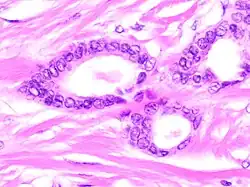

Tubular carcinomas are generally around 1 cm. or smaller, and are made up of tubules. They are usually low-grade.[2] Elastosis has been noted as common but is not present in all cases.[11]

A highly differentiated invasive carcinoma that forms well-defined tubules (containing epithelium, but no myoepithelium) and that have abundant desmoplastic fibrous stromal reaction between the tubules.